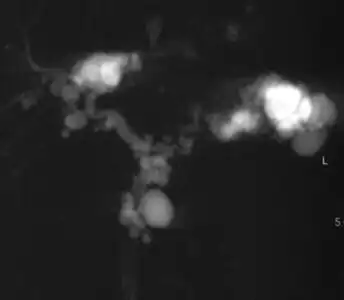

Magnetic resonance cholangiopancreatography (MRCP) of Caroli disease, showing cystic dilatations of bile ducts.[1]

| Turbo spin echo T2-weighted axial MRI of Caroli disease, showing cystic dilatations of bile ducts (shown as white).[1] | |